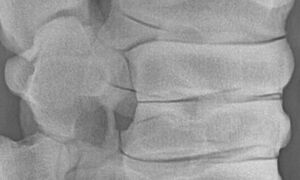

Digitales Röntgen

Röntgenaufnahme einer Pferdewirbelsäule

Zur Beurteilung des Skelettsystems.